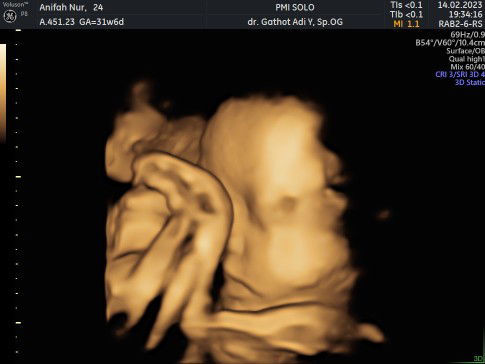

Usg Jenis kelamin

Kira2 berapa bulan USG bisa lihat hasil JK calon debay 🥰